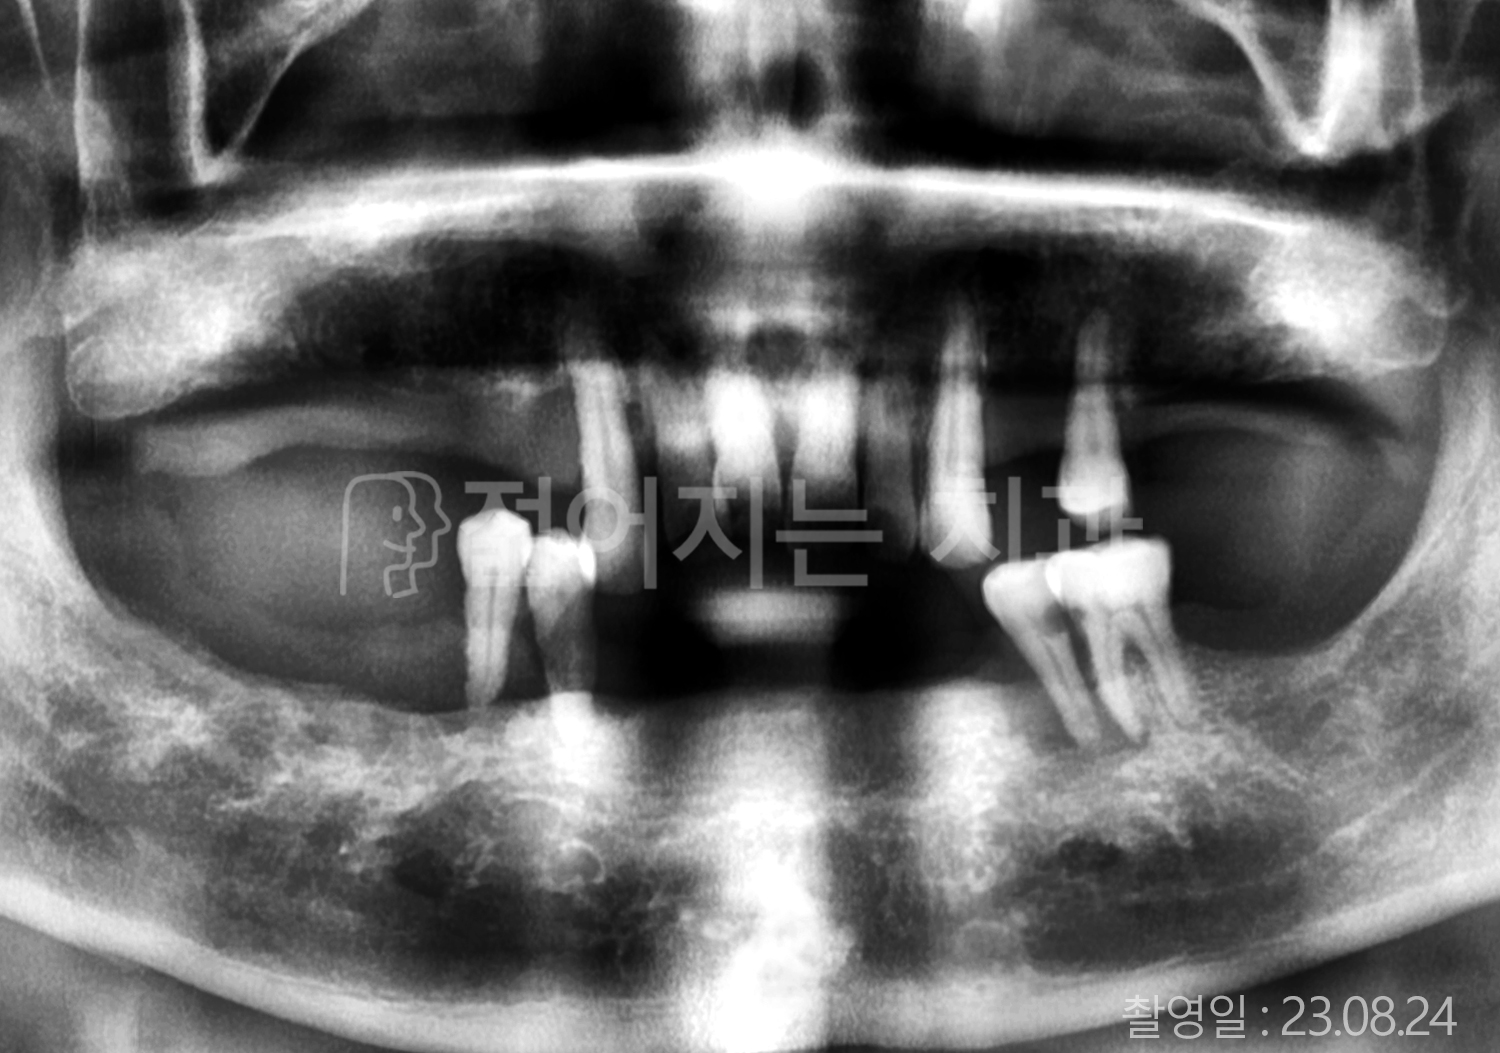

• 60대 고혈압, 고지혈증 전체치아 10개 이상 임플란트

• 70대 전체치아 10개 이상 임플란트

• 60대 전체치아 10개 이상 임플란트

• 50대 전체치아 10개 이상 임플란트

• 50대 고혈압, 고지혈증 전체치아 10개 이상 임플란트

• 60대 고혈압, 당뇨, 고지혈증 전체치아 10개 이상 임플란트

• 80대 고혈압, 당뇨, 골다공증 전체치아 10개 이상 임플란트

• 60대 고혈압 전체치아 10개 이상 임플란트

• 60대 고지혈증 전체치아 10개 이상 임플란트

• 60대 당뇨 전체치아 10개 이상 임플란트